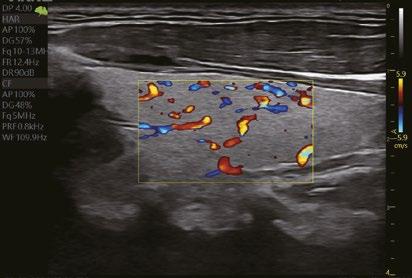

Erkennung der Fließgeschwindigkeit des Blutes. Es ermöglicht eine feinere Diagnose, bei besonders schwierigen Untersuchungen des Blutflusses.

Eine innovative Technologie, die die Visualisierung des Blutflusses verbessert, indem sie eine 3D-Darstellung der Farb-/Power-Doppler-Bildgebung anzeigt.

Karotis-CF

Schilddrüse CF